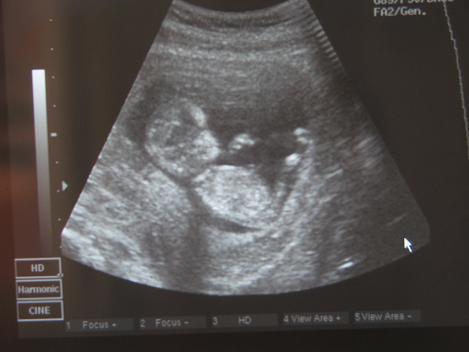

Tegnap megkukkoltuk pici juhart! Fejen állva produkálta magát! Járt keze, lába,ugrált. Most 59 mm. Ma reggel meg megcsapoltak rendesen. 5 kémcső vért vettek le. Azért leültem utána váróba nehogy rosszul legyek. De hálistennek nem lettem.Ja és ma 1 hete már nem is hánytam! :D

És akkor pici juhar :D

Kép

Juhar, te minket becsaptál! Nincs is levél formája a babának! Tök olyan, mint egy pici emberke. :wink: Édes nagyon!